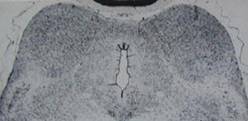

Oxygen insufficiency at birth damaged nuclei in

the midbrain auditory pathway.

anoxic damage